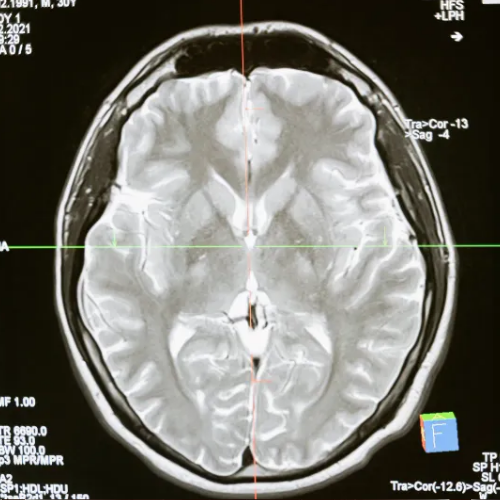

병원을 찾아 뇌 MRI, CT 등 여러 검사를 받아도 특별한 이상이 발견되지 않는 경우가 많고,

이는 어지럼증의 원인을 주로 뇌나 귀의 구조적 문제에만 초점을 맞춰 진단하기 때문입니다.